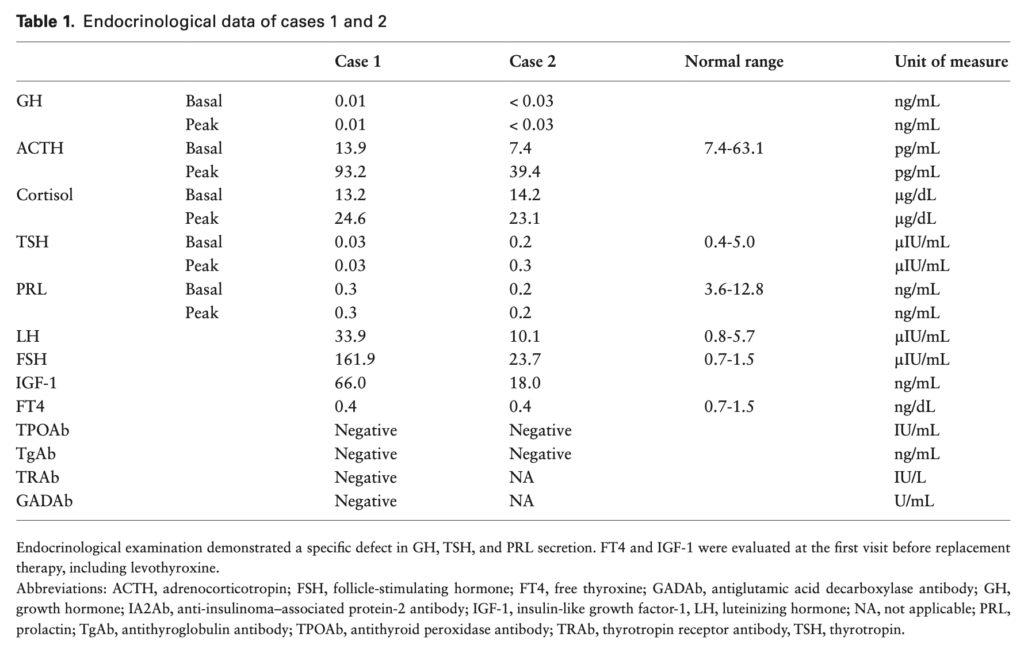

追加検査を行うとPRL・GHが検出下限値を示す。ACTHやLH・FSHは正常。

①後天的なGH・PRL・TSHの特異的な欠乏

内分泌学的所見では、GH・PRLが検出下限以下で、TSH・IGF-1・fT4が低値を示す。

負荷試験でこれらのホルモンの反応が悪い。

他の下垂体ホルモンの分泌の障害がない。

下垂体MRIでは明らかな異常が認められないため、原因不明の中枢性甲状腺機能低下症と診断されることが多い。しかし、造影MRIを行うと一部の患者では不均一な増強を伴うわずかに萎縮した下垂体前葉が認められる。